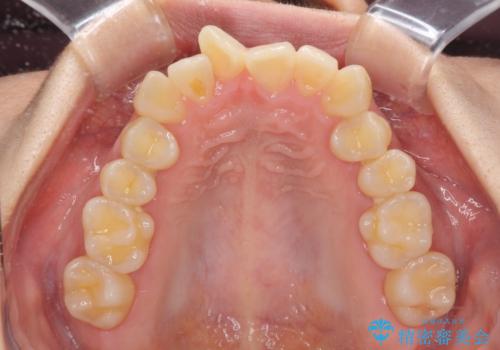

当初は上記計画でしたが、レントゲン撮影よりインプラント埋入は困難と判断され、患者様と相談の上、歯を削ってブリッジとするよりも、奥歯の咬み合わせを多少妥協することとなっても、スペースを閉じて仕上げていくこととしました。

1年弱で治療方針を変更したため、治療期間は長くなりましたが、スペースは無事に閉じ、咬合の違和感なく仕上げることができました。

ただし、両方の臼歯部は理想的な咬合とは言えないため、咬合による歯の外傷を防ぐため、就寝時にはマウスピースを継続使用するようお願いしております。